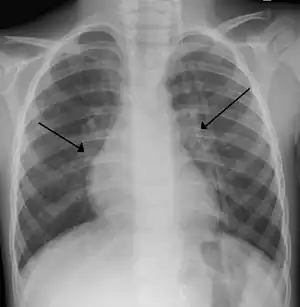

X-ray of a child with RSV bronchiolitis showing the typical bilateral perihilar fullness

Chest x-rays findings in children with RSV bronchiolitis are generally nonspecific and include perihilar markings, patchy hyperinflation, and atelectasis.[16] However, the American Academy of Pediatrics (AAP) does not recommend routine imaging for children with presumed RSV bronchiolitis because it does not change clinical outcomes and is associated with increased antibiotic use.[16][35] Chest x-ray is sometimes considered when the diagnosis of bronchiolitis is unclear or when there is an unexpected worsening.[35] In adults with RSV infection, chest films are often normal or demonstrate nonspecific changes consistent with viral pneumonia, such as patchy bilateral infiltrates.[38]